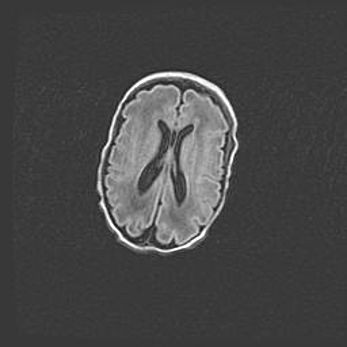

Наружная гидроцефалия с возможной атрофией височных областей.

Возраст: 28 дней

Вес: 3670 г

Пол: мужской

Окружность головы: 38 см

Срок гестации: 40 недель

Гидроцефалия головного мозга у новорожденных – это заболевание, которое характеризуется скоплением избыточного количества спинномозговой жидкости в желудочковой системе головного мозга в результате затруднения её перемещения от места выработки к месту поглощения в кровеносную систему или вследствие нарушения абсорбции. При открытой наружной форме гидроцефалии у новорожденных расширяются и переполняются субарахноидные пространства.

При нормотензивных  формах,  которые,  как  правило,  являются  следствием  перенесенных ишемических  повреждений  паренхимы  мозга,  возможно  сочетание микроцефалии  с нормотензивной гидроцефалией. В основе данных изменений лежит атрофия больших полушарий с преимущественной  локализацией  в  лобно-височных  областях.